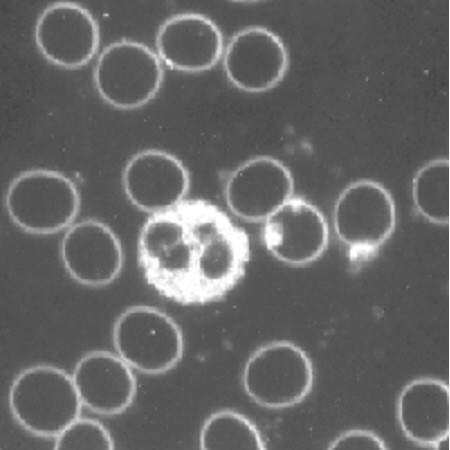

Vitalblutanalyse im Dunkelfeld

Mit Hilfe eines Spezialmikroskopes untersuche ich einen Tropfen Kapillarblut, den ich aus dem Finger oder Ohrläppchen entnehme.

Die Dunkelfelddiagnostik gibt Hinweise auf

- krankhafte Veränderungen der Blutzellen

- Störungen der Durchblutung

- Sauerstoffmangel

- Störungen des Stoffwechsels und der Säure-Basen-Balance

- chronische Entzündungen

- Darmbelastungen

-Nierenstörungen

- Belastungen von Leber und Galle

- Fettverwertungsstörungen

- Vitamin B12 und Folsäure Mangel

- parasitäres Geschehen

- Immunfunktion

- degenerative Tendenzen usw.